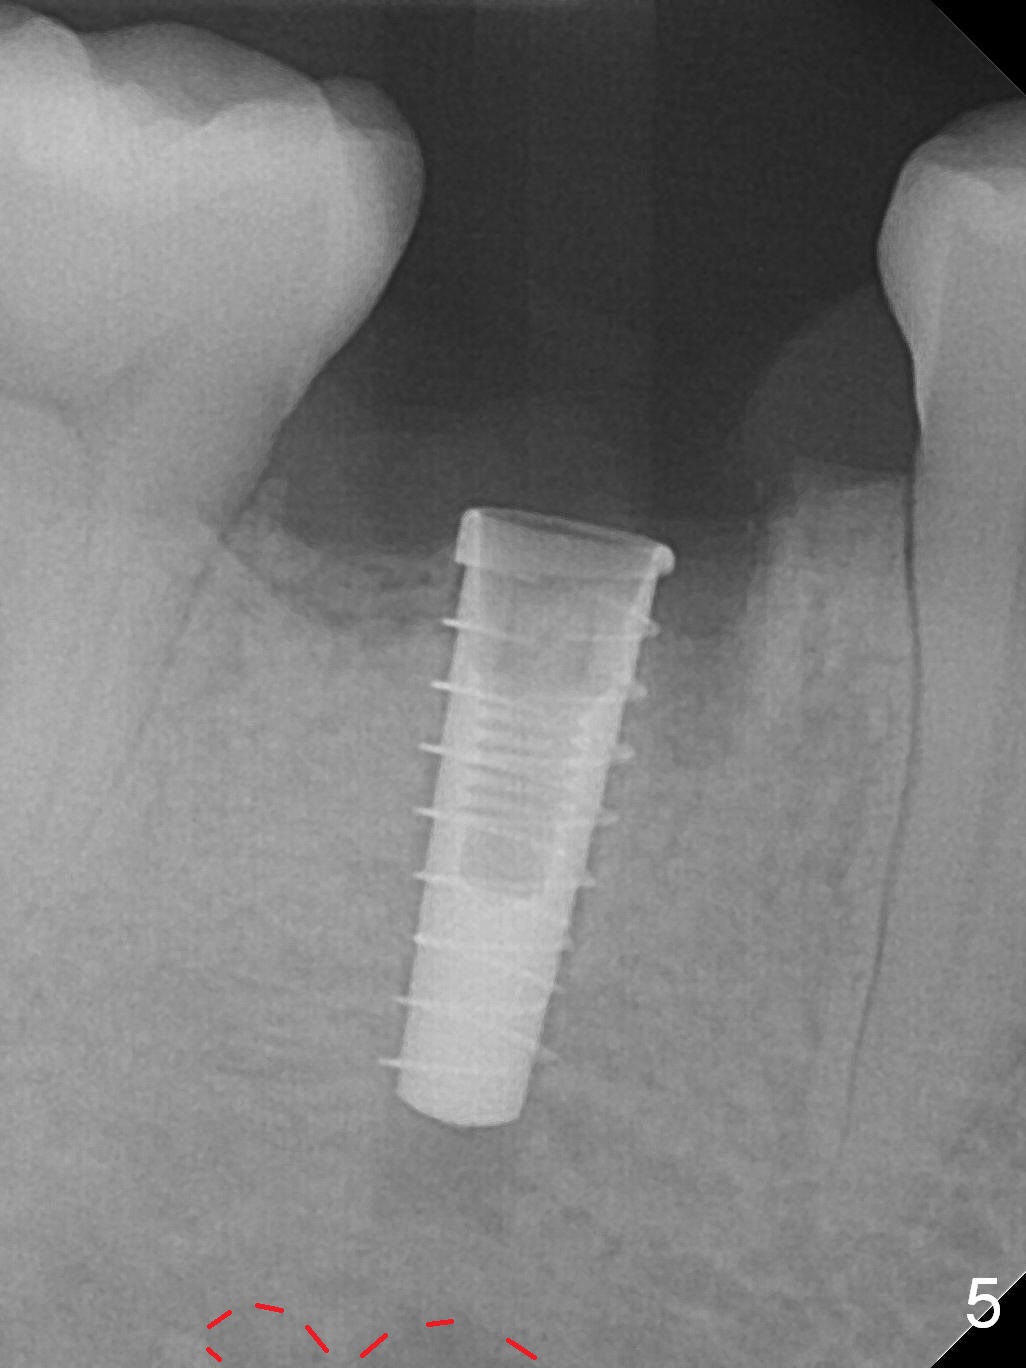

The lower 2nd primary molar has buccal furca lesion (Fig.1 *) with the thin buccal plate (Fig.2). Osteotomy is initiated in the sloped septum (Fig.3). After use of Magic Drill (MD) 3.3 mm for 13 mm and MD 3.8 mm for 11 mm, placement of a 4x11 mm IBS implant meets resistance because of the dense bone (Fig.4-6, red dashed line: Mental Loop) with final insertion torque >50 Ncm. After placement of a 6x4(3) mm abutment and autogenous bone in the remaining shallow sockets (Fig.6), a provisional is fabricated (Fig.7). Finally periodontal dressing is applied. Impression is taken 3 months postop (Fig.8). Buccal infection develops 2 weeks post cementation (Fig.9). When the crown/abutment is removed, there is no residual cement. The implant threads can be felt through the fistula. After soft tissue debridement and copious irrigation, Arestin is placed in the fistula. The latter disappears 15 days post debridement. The patient feels better and moves out of state. It appears that early periimplantitis develops because of the preexisting buccal furca lesion and failure to place the implant deep. The implant will be placed deep after loosening a little (since there is apical space (Fig.8 white line)) or removed, truncated at the apex and placed lower than the buccal crest.